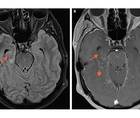

Case Report: Seizure, Fever, Hallucinations, & Vision Loss

Elizabeth Carroll, MD; Brian J. Williams, MDElizabeth Carroll, MD; Brian J. Williams, MD - Epilepsy & Seizures